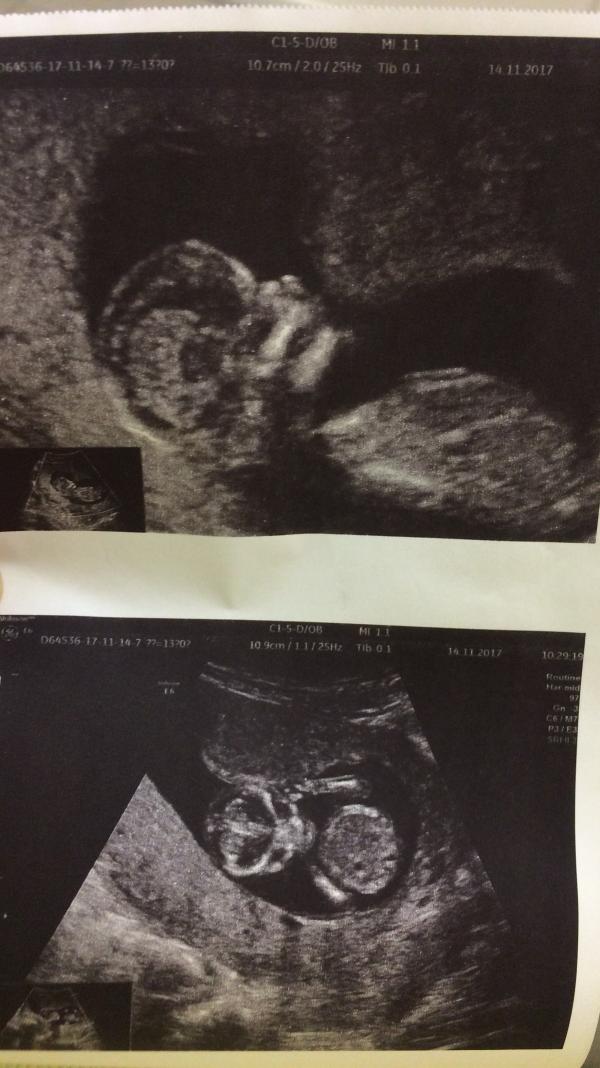

Йеху! Первый скрининг пройден! Всё отлично: слышала сердце, видела мозг, позвоночник, рёбрышки😍 Расти здоровым, красивым, умным, наш инопланетянин ❤️ Срок: 13,5 акушерских недель

(Роддом), узист смотрела сначала сама экран, сердце включала, а после своей проверки повернула экран ко мне и стала говорить: что недели соответствуют, всё в норме, вот смотрите :вот мозг, вот позвоночник, вот сердце, ручки, глазки и т.д. Даже дала два снимка на память, я уже и не рассчитывала на снимки в бесплатной, но дали) Так что лежите спокойно и ждите когда покажут) не переживайте)

Как мило ... так видно хорошо , моя уворачивалась и на втором и на третьем )